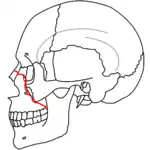

Le Fort II fractures

At the beginning of the 20th century, René Le Fort mapped typical locations for facial fractures; these are now known as Le Fort I, II, and III fractures (right).[7] Le Fort I fractures, also called Guérin or horizontal maxillary fractures,[14] involve the maxilla, separating it from the palate.[15] Le Fort II fractures, also called pyramidal fractures of the maxilla,[16] cross the nasal bones and the orbital rim.[15] Le Fort III fractures, also called craniofacial disjunction and transverse facial fractures,[17] cross the front of the maxilla and involve the lacrimal bone, the lamina papyracea, and the orbital floor, and often involve the ethmoid bone,[15] are the most serious.[18] Le Fort fractures, which account for 10–20% of facial fractures, are often associated with other serious injuries.[15] Le Fort made his classifications based on work with cadaver skulls, and the classification system has been criticized as imprecise and simplistic since most midface fractures involve a combination of Le Fort fractures.[15] Although most facial fractures do not follow the patterns described by Le Fort precisely, the system is still used to categorize injuries.[5]